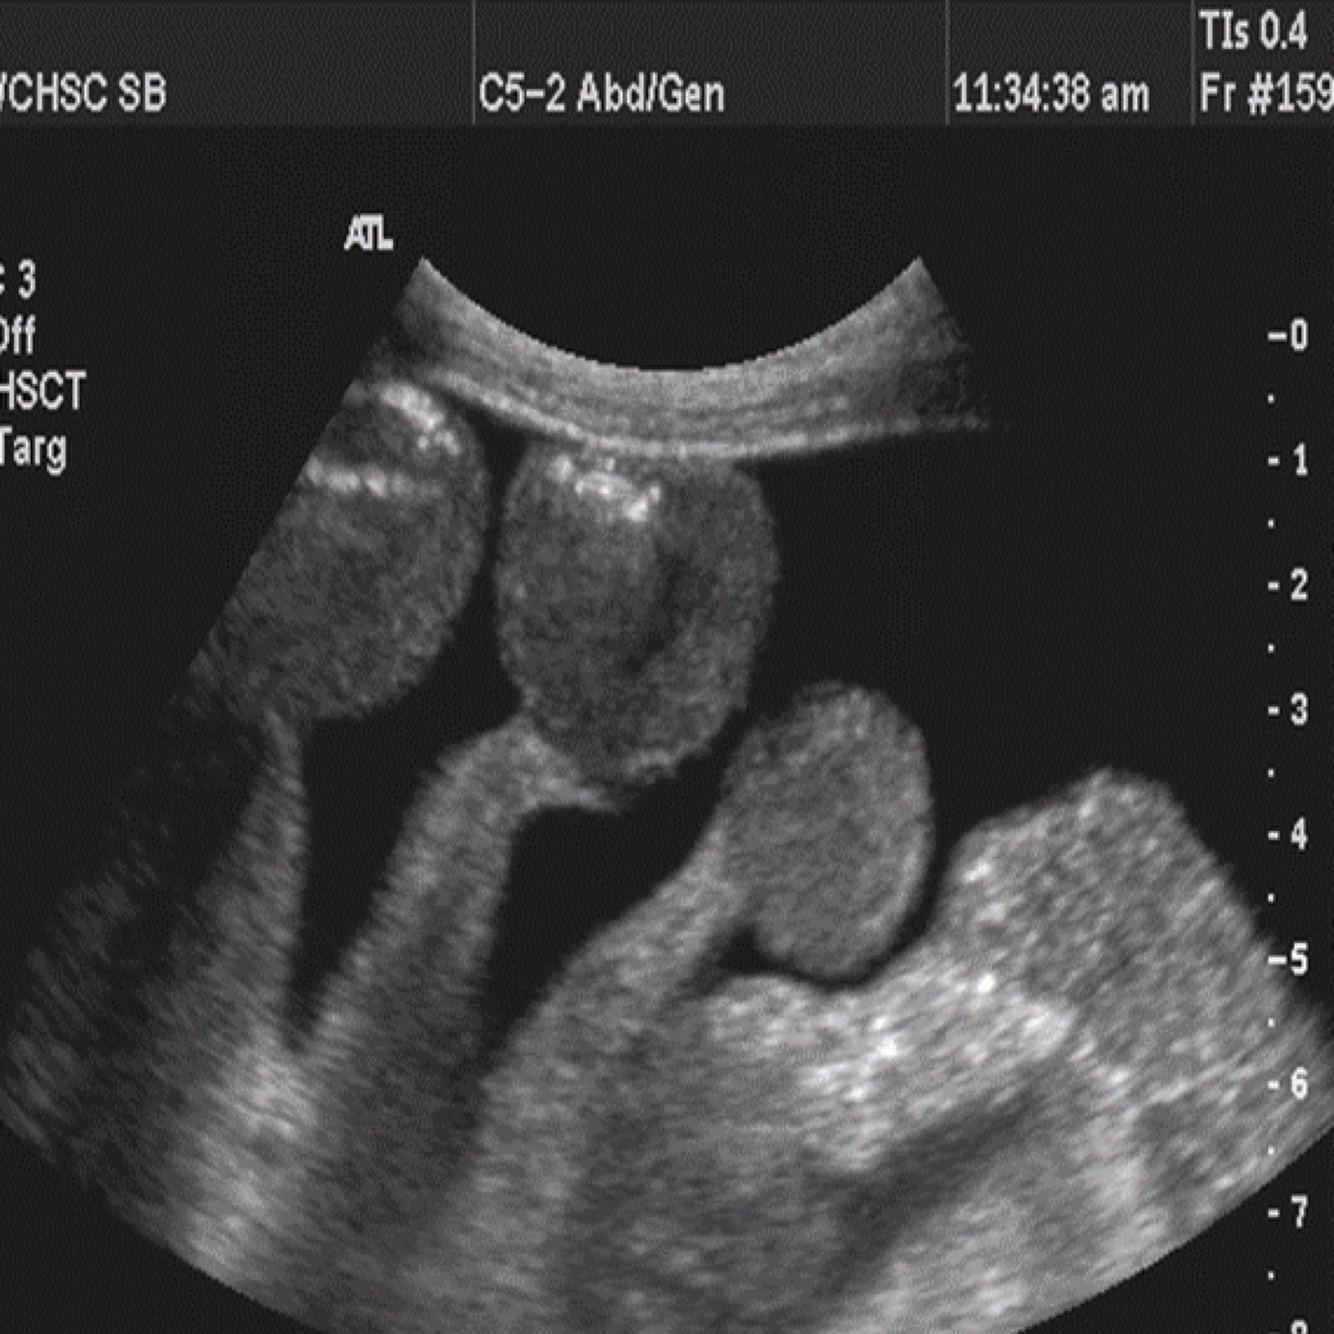

Q

The image represents what?

A

Dilated calyces and renal pelvis